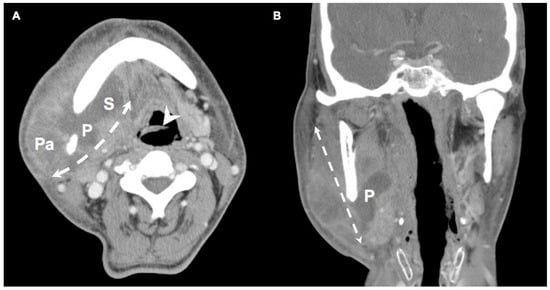

Figure 1.

(A) Axial view and (B) coronal view of a DNI patient with DM. (A) indicates that the infection spread from the parapharyngeal space to the parotid space and the submandibular space, encompassing infection across multiple deep neck spaces. (B) depicts infection in the coronal plane. Arrowhead: epiglottis; Double dotted arrow: involved spaces of DNI; P: parapharyngeal space; Pa: parotid space; S: submandibular space. (300 × 300 dpi).